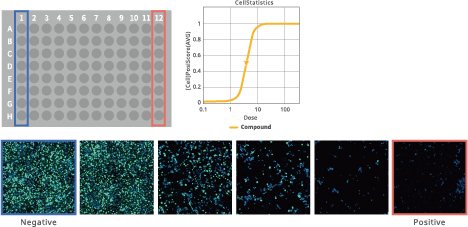

EC50/IC50 calculation (deep image response)

Image Credit: Yokogawa Life Science

Using whole images, this function allows for the thorough quantification of complicated phenotypes. Simple process of entering compound concentration data and choosing positive and negative wells. There is no need for any process to segment cells.

EC50/IC50 calculation (deep image response)

Image Credit: Yokogawa Life Science

This feature makes it possible to use whole images to measure complicated phenotypes thoroughly. Choosing positive and negative wells and entering information regarding compound concentration is simple. Segmentation of cells does not require any methodology.

Improved EC50 calculation